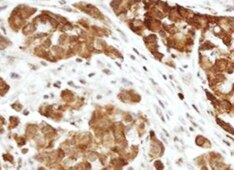

PTGER1 in Human Breast Cancer Tissue. PTGER1 was detected in immersion fixed paraffin-embedded sections of human breast cancer tissue using Mouse Anti-Human PTGER1 Monoclonal Antibody (Catalog # MAB100081) at 5 µg/mL for 1 hour at room temperature followed by incubation with the Anti-Mouse IgG VisUCyte™ HRP Polymer Antibody (Catalog # VC001). Before incubation with the primary antibody, tissue was subjected to heat-induced epitope retrieval using Antigen Retrieval Reagent-Basic (Catalog # CTS013). Tissue was stained using DAB (brown) and counterstained with hematoxylin (blue). Specific staining was localized to cytoplasm. View our protocol for IHC Staining with VisUCyte HRP Polymer Detection Reagents.